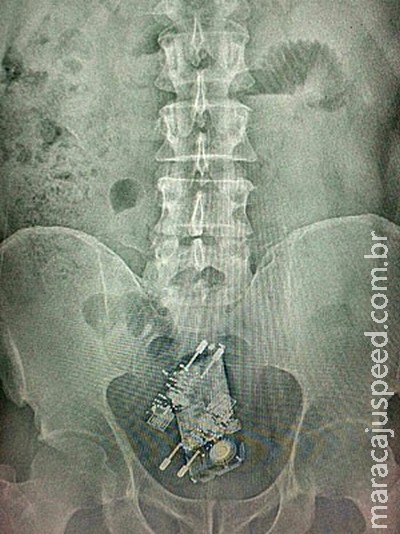

Um detento da Papuda, em Brasília, foi flagrado com um celular e dois carregadores no reto ao retornar à penitenciária após o Saidão do Dia das Crianças, na manhã desta terça-feira (13). O aparelho de raio X identificou os objetos.

Segundo a Secretaria de Justiça e Cidadania do DF, o presidiário foi levado para o Hospital Regional da Asa Norte (Hran), onde passou por cirurgia para a retirada dos objetos.

Os aparelhos estavam embalados em plástico dentro do corpo do homem. A secretaria não informou por que o detento estava na unidade. Presos que cometerem infrações durante o período e forem pegos em flagrante perdem todos os direitos já alcançados e a pena do novo crime soma-se às outras.